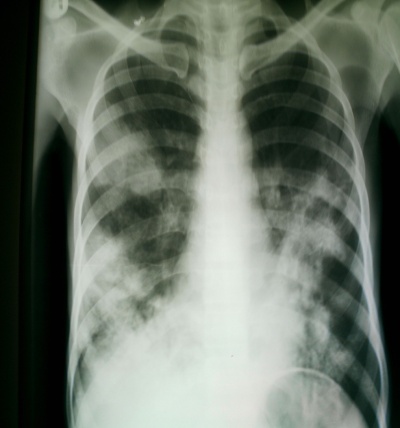

It is important to acknowledge the role of X-ray imaging in the diagnosis of paucibacillary HIV/PTB co-infection and difficult-to-diagnose extrapulmonary TB, since high-tech diagnostic tools such as polymerase chain reaction and nucleic acid line probes are not yet available in our clinic.

Bilateral soft nodular opacities worse in both lower lobes

Right sided pleural effusion with nodular opacities